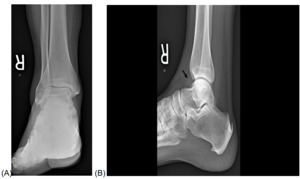

An AP, lateral, and oblique image was performed on the right ankle 2 days after the injury (Figure 1A, 1B). No fracture was evident; however, there was prominent soft tissue swelling, most prominent overlying the lateral malleolus, with evidence of mortise-joint effusion. One week later, a repeat radiographic examination was performed to exclude an occult fracture. The patient’s pain persisted, and 1 week later, images were repeated (Figure 2A, 2B). New radiographs demonstrated mildly reduced swelling of the ankle and mild mortise-joint effusion. MRI was recommended to help assess for possible internal joint derangement.

_and_lateral_(b)_ankle_radiographs_10_days_after_injury.png)